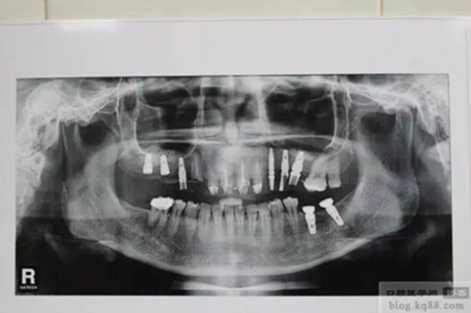

上前牙做充填和纖維樁修復(fù)后左上后牙內(nèi)提升植入三顆植體

上圖為術(shù)后1年X光片 上基臺